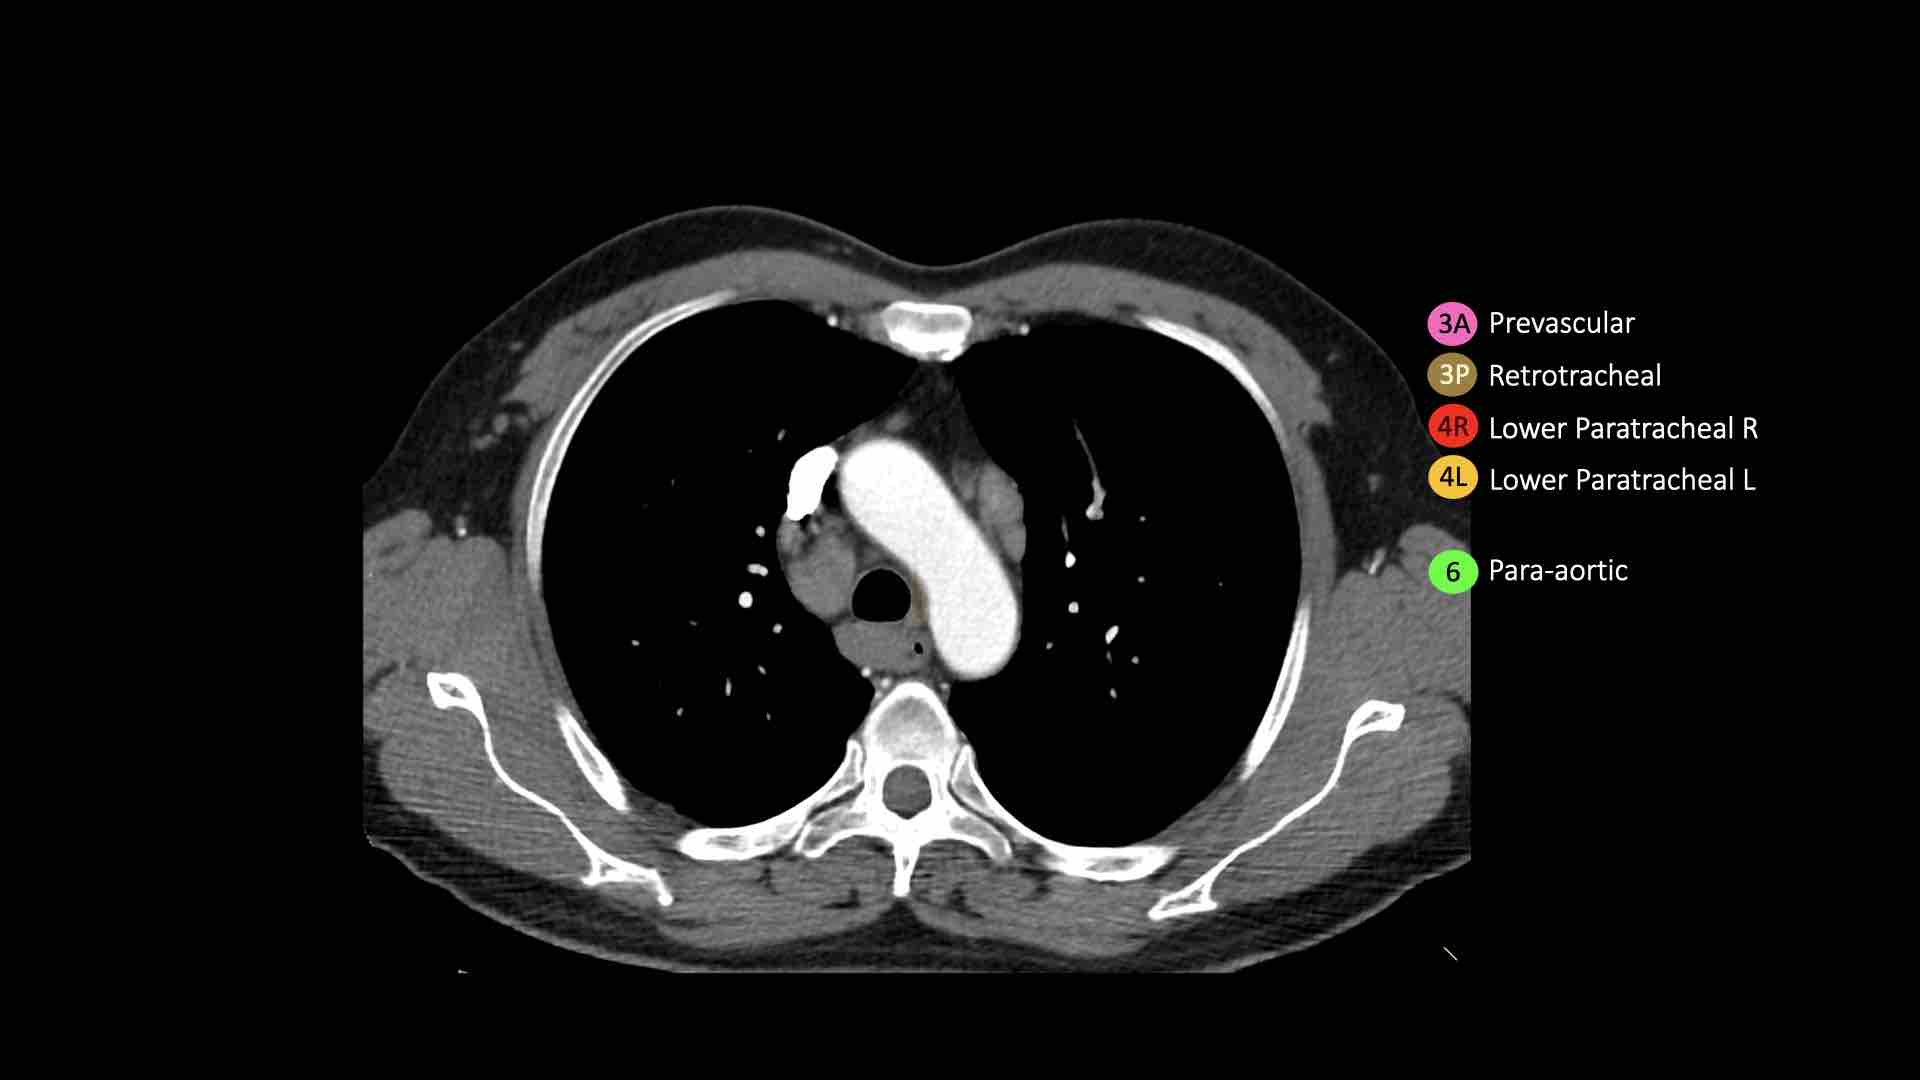

4L. Hạch cạnh khí quản dưới bên trái

Hạch nhóm 4L là các hạch cạnh khí quản dưới nằm bên trái bờ trái của khí quản, giữa đường nằm ngang tiếp tuyến với bờ trên quai động mạch chủ và đường tiếp tuyến với bờ trên động mạch phổi trái.

Nhóm này bao gồm các hạch cạnh khí quản nằm ở phía trong dây chằng động mạch.

Hạch nhóm 5 (cửa sổ phế động mạch) nằm ở phía ngoài dây chằng động mạch.

Bên trái là hình ảnh ngay trên mức thân động mạch phổi, cho thấy các hạch cạnh khí quản dưới bên trái và bên phải.

Ngoài ra còn có các hạch nhóm 3 và nhóm 5.

Bên trái là hình ảnh ở mức phần dưới khí quản, ngay trên carina.

Bên trái khí quản là các hạch 4L.

Lưu ý rằng các hạch 4L này nằm giữa thân động mạch phổi và động mạch chủ, nhưng không nằm trong cửa sổ phế động mạch, vì chúng nằm ở phía trong dây chằng động mạch.

Hạch nằm bên ngoài thân động mạch phổi là hạch nhóm 5.